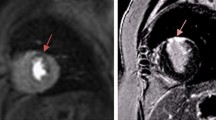

A total of 7/31 (23%) patients had a perfusion deficit on the first-pass perfusion images. None of the patients demonstrated an abnormality on delayed myocardial enhancement imaging without a corresponding perfusion deficit. Five of the seven patients with abnormal perfusion had a concomitant wall motion abnormality, whereas none of the patients with normal perfusion had a wall motion abnormality. Three of the seven patients with abnormal perfusion had an irreversible perfusion defect. The first patient had a diagnosis of D-TGA with a Yacoub type D coronary pattern, was lost to follow-up for more than 5 years, and subsequently presented with ST changes on resting and exercise ECG testing. The stress perfusion images are seen in Fig. 2. The defect was thought to be irreversible because of the extent of the delayed enhancement that corresponded to the perfusion defect (Fig. 2). Coronary angiography at cardiac catheterization demonstrated complete occlusion of the circumflex artery. The second patient with an irreversible perfusion defect had undergone unroofing for anomalous origin of the right coronary artery from the left sinus of Valsalva. The final patient with an irreversible defect had Kawasaki disease with an aneurysm at the bifurcation of the left anterior descending and circumflex coronary arteries. During cardiac catheterization that followed the cardiac MR, he was found to have near-occlusion of the circumflex coronary artery and severe stenosis of the proximal left anterior descending coronary artery. Four additional patients were found to have inducible myocardial ischemia with stress perfusion. Two of these patients had Kawasaki disease, one of whom had undergone right and left internal mammary bypass grafts (Fig. 3). Another patient had previously undergone an arterial switch operation for D-TGA and was found to have a reversible defect of the interventricular septum after complaining of chest pain with exertion. The final patient had undergone an aortic root replacement from a peri-aortic abscess; she was diagnosed after complaining of chest pain while hiking.

Cardiac MR in the left ventricular short-axis plane at the mid-ventricular level in an 18-year-old man diagnosed with D-transposition of the great arteries status post arterial switch operation. a Stress perfusion image demonstrates a pattern of decreased signal at the inferior and inferolateral walls, consistent with abnormal perfusion. b Delayed hyperenhancement image demonstrates increased signal in the inferior and inferolateral walls, corresponding to the area of abnormal perfusion seen in (a)